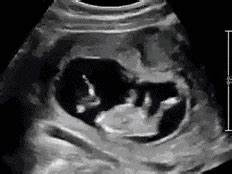

四、如何发现与应对?

产检手段:B超可检出,胎心监护观察异常波动。

孕妈能做的:

√ 数胎动(异常增减需就医)

× 避免盲目做"绕颈矫正操"(无科学依据)